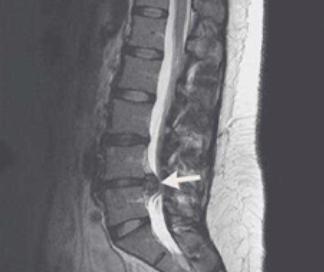

Tout d'abord, lorsqu'il s'agit de lombalgie, presque tout le monde pense à un type de maladie, à savoir la hernie discale lombaire. En fait, certaines personnes ne vont pas aussi loin que la hernie discale lombaire, les disques lombaires bombés peuvent également faire souffrir le dos d'une personne. Dans ce cas, il faut dire que la personne sera particulièrement apte à produire la sensation de mal de dos. Si, par exemple, après une journée passée en position assise ou debout, on ressent des douleurs lombaires, qui irradient parfois jusqu'aux cuisses, il pourrait s'agir de la hernie discale lombaire ou du bombement discal mentionnés ici. Ne l'ignorez pas pour l'instant, il est préférable d'effectuer une IRM de la colonne lombaire pour obtenir un diagnostic clair.

Si votre ami est victime d'un traumatisme, d'une pathologie de la colonne lombaire (hernie discale lombaire, prolapsus, fracture, ostéophyte) causant une lombalgie, vous devez vous rendre à l'hôpital ordinaire pour un traitement symptomatique, tout en renforçant les soins quotidiens et en renforçant de manière appropriée l'exercice physique, ce qui contribuera à la guérison et à la réduction de la douleur.